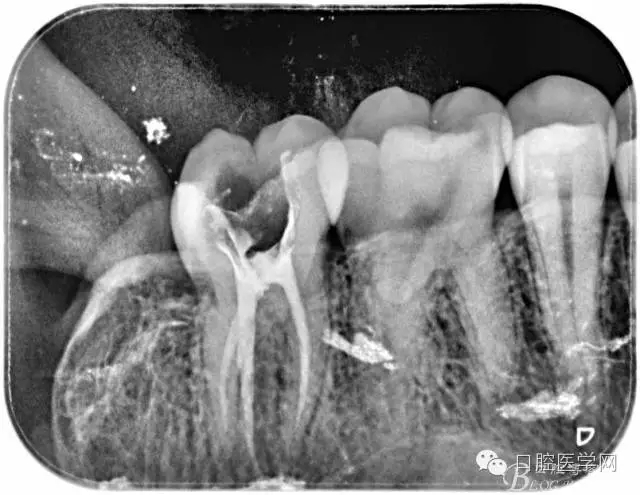

根管的解剖界限是从髓室根管入口到根尖部牙本质- 牙骨质交界处(生理性根尖孔) 。理想的根管充填应该是对生理性根尖孔冠方以上进行严密的三维封闭。临床上根据X线牙片判断根管充填的质量。牙片上充填材料与根管壁紧密接触一般被认为充填严密。关于充填止点,由于牙本质- 牙骨质界离根尖孔外表面平均距离为0. 5~0. 7 mm,同时相当多的根尖开口并不位于X线片的根尖处。因此临床上认为材料充填至距X线片牙根最尖端0. 5~1 mm (也有认为0. 5~2mm)为适填。

为达到更为理想的根充效果,研究人员和牙髓病医生一直在探索根管充填技术,并且发展出多种可供选择的方法。Ingle]将其归纳为3 类: ①“牙胶尖+封闭剂”式; ②“根尖1 /3充填”式; ③“注射或螺旋充填”式。目前临床广泛采用的主要是“牙胶尖+封闭剂”方式。按照充填压力的方向(侧向或垂直)不同和牙胶温度(冷或热)不同,根管充填有2 种基本技术:冷牙胶侧方加压充填和热牙胶垂直加压充填。现有的各种充填方法均是这2 种基本方法基础上的发展或改良。医生可根据方法的优缺点以及个人习惯选择使用。

6、封闭剂使用